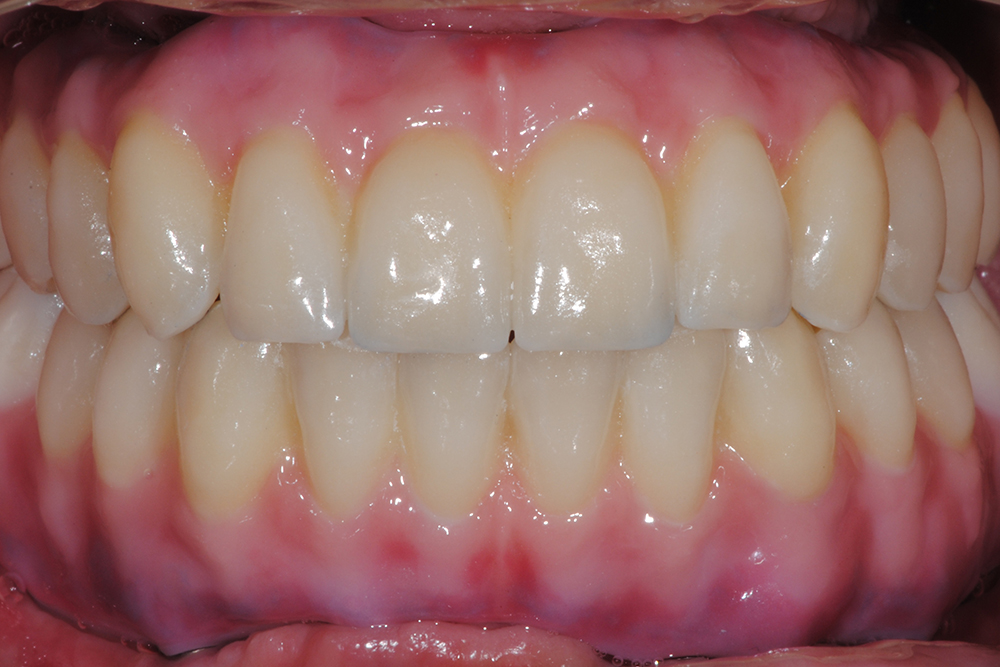

Ripristino dell'arcata superiore ed inferiore su impianti con ricostruzione estetica in zirconia e ceramica Category: Lavori ImpiantiMaggio 9, 2018Condividi questo ProgettoShare with FacebookShare with TwitterShare with Google+Share with PinterestShare with LinkedInProject navigationPreviousPrevious project:Ripristino dell’arcata superiore atroficaNextNext project:Protesi mobile superiore + Overdenture inferiore